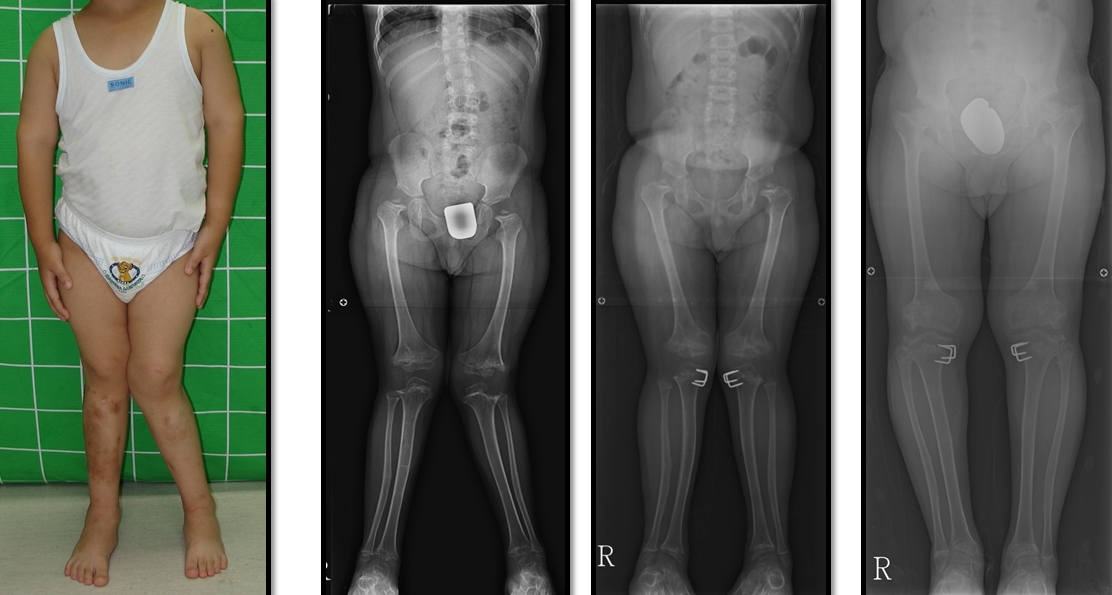

공지 다발성골단이형성증환자의 하지변형에 대한 교정 3관리자-다발성골단이형성증으로 다리가 밖으로 휘어 교정술을 받고 정상적인 다리모양이 되었습니다. Correct valgus deformity caused by epiphyscaldisplasia, resulting normal leg shape.다음글공지 비타민디저항성구루병환자의 하지변형에 대한 교정 ..이전글공지 다발성골단이형성증환자의 하지변형에 대한 교정 2목록